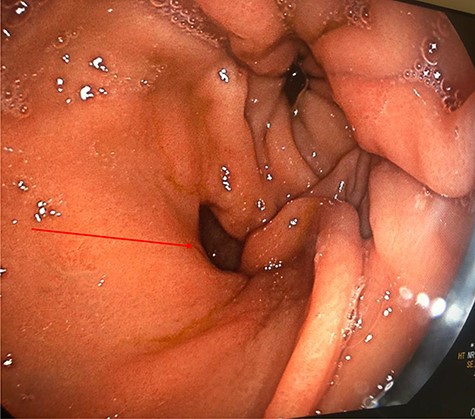

Computed tomography (CT) revealed a complex fistulous communication between the distal stomach and biliary tree with associated pneumobilia, and between the transverse colon and the distal stomach (Fig. 1). No gallstones were seen. Upper and lower gastrointestinal endoscopy was performed, revealing a prepyloric gastric ulceration and fistula (Fig. 2), with no obvious gastric pathology, which extended into the colon and a blind end structure assumed to be the gallbladder. Colonoscopy demonstrated an area of slight narrowing from the hepatic flexure to mid-transverse colon, with macroscopic colitis (Fig. 3). Biopsies were non-specific, with IBD a possibility, but the features were not pathognomonic.

CT abdomen and pelvis demonstrating fistulous communication between distal stomach and transverse colon (red arrow) with pneumobilia.